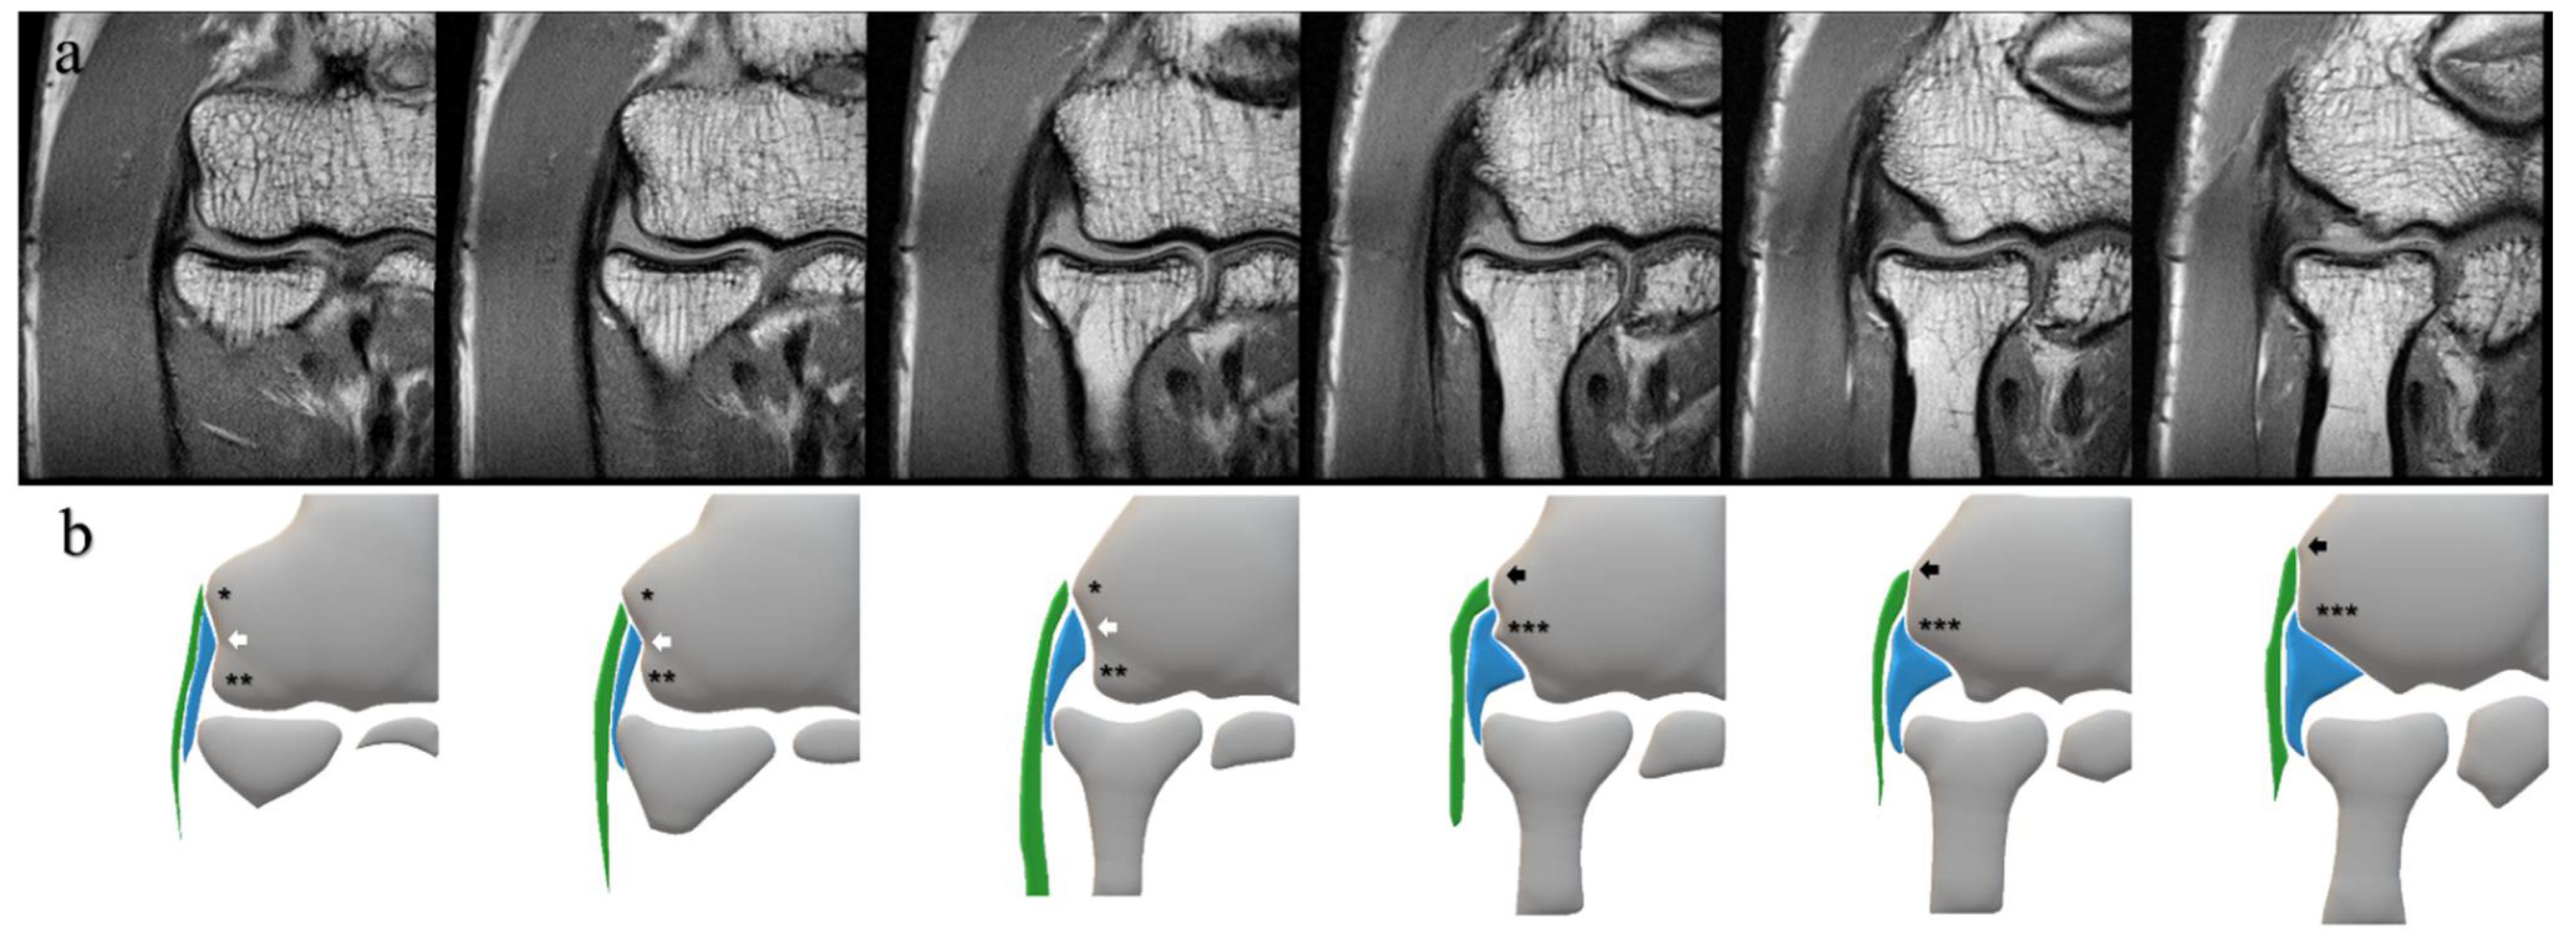

Our protocol provided a clear and enlarged view of the lateral aspect of the elbow; we could recognize the CET and the LCL as rather isolated structures. Furthermore, we used bony landmarks to define the CET and the LCL independently (Figure 2) [25,26]. In the coronal MRI images, we defined the CET as the structure attached to the superior tubercle or the epicondylar ridge and the LCL as the structure attached to the intertubercular sulcus or the inferior surface of the posterior tubercle.

Figure 2.

Consecutive MRI slices under PDWI of the unaffected lateral elbow (a) and corresponding schemas (b). These schemas represent bony landmarks and the CET and the LCL in this study. * superior tubercle; ** anterior tubercle; *** posterior tubercle; white arrow, intertubercular sulcus; black arrow, epicondylar ridge; green area, CET; blue area, LCL; MRI, magnetic resonance imaging; PDWI, proton-density-weighted imaging; CET, common extensor tendon; LCL, lateral collateral ligament.